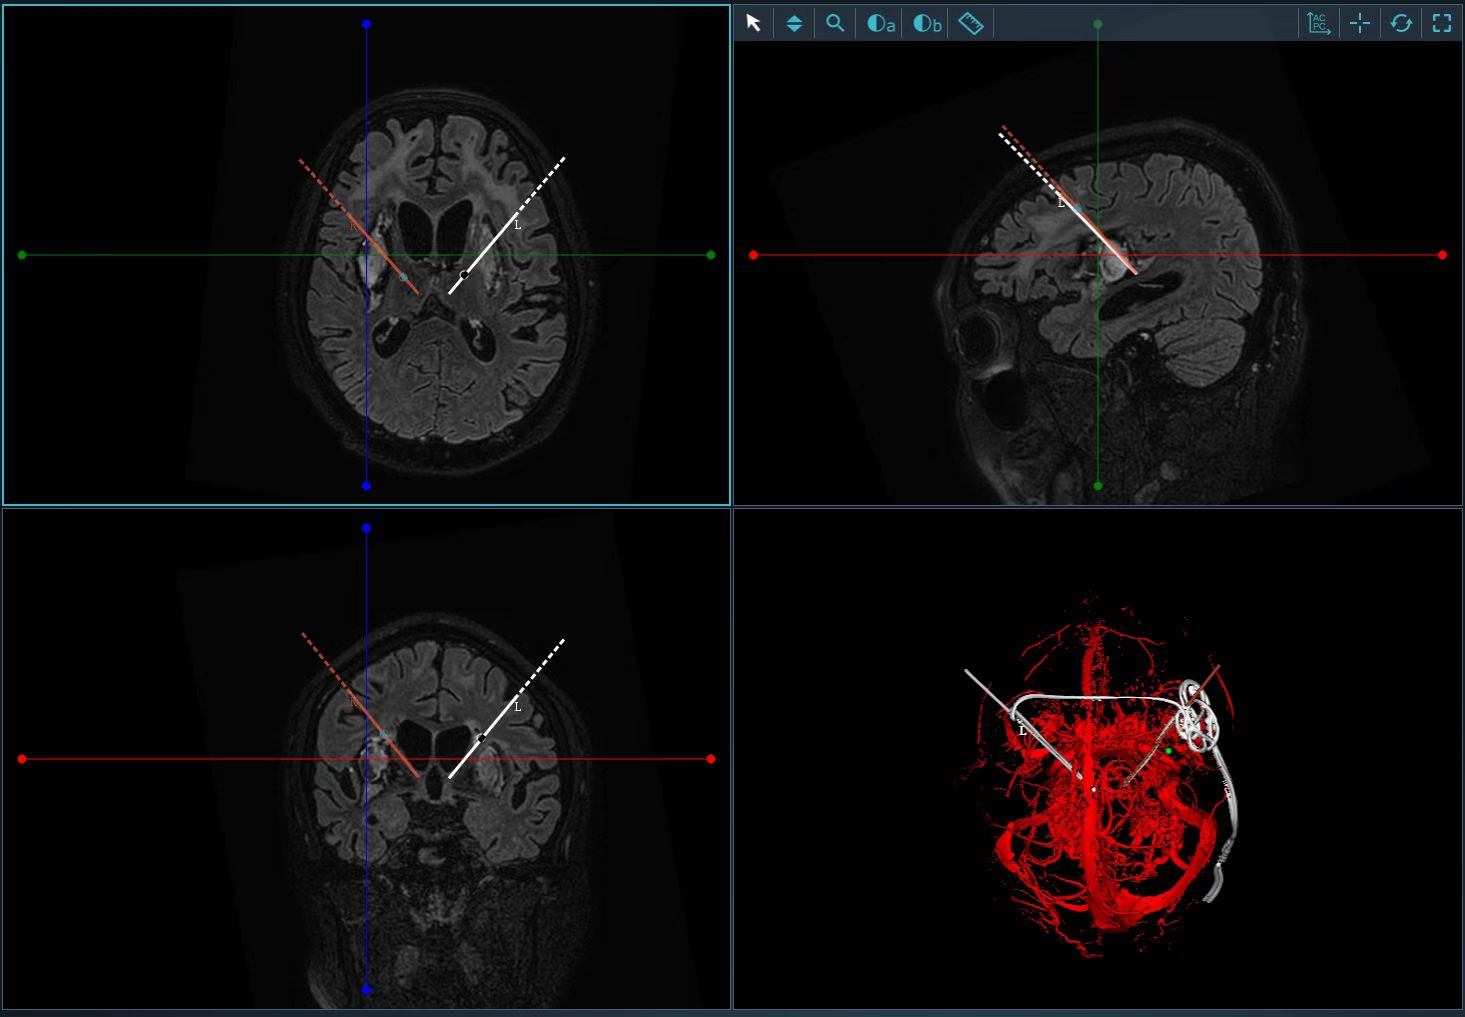

8月15日,杨靓团队顺利为患者行DBS促醒手术。术中,通过立体定向框架结合电脑软件分析精准定位并验证,在一步步毫厘不差的精细操作下,精准定位穿刺点并控制穿刺深度,将两根微电极精准植入彭某大脑深部中央丘脑核团,电极植入精度均在0.15mm以内。